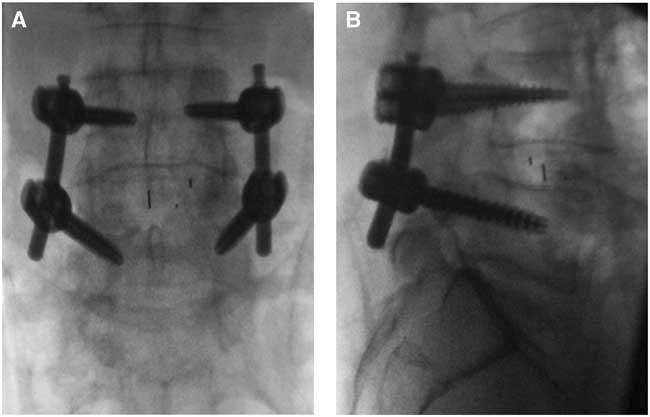

The patient underwent an uncomplicated L4-L5 posterior microdecompression (bilateral decompression via a unilateral approach with preservation of the spinous process and contralateral lamina) under microscopic visualization with L4-L5 minimally invasive transforaminal lumbar interbody fusion using a PEEK (Stryker; Hamilton, ON, Canada) banana-shaped cage and local bone graft. Instrumentation was augmented with bilateral cannulated percutaneous pedicle screw fixation placed using a combination of computer assisted three-dimensional navigation and fluoroscopy (Figure 2A, B). Neuromonitoring with electromyography, somatosensory-, and motor-evoked potential was used throughout and did not indicate any nerve encroachment. There was no excessive manipulation of the nerve roots for the decompression or cage insertion. Care was taken to ensure the dura was intact before final closure, including Valsalva maneuver, which did not elicit any cerebrospinal fluid leak. Bleeding was well controlled with bipolar electrocautery and Floseal (Baxter Corporation; Mississauga, ON, Canada) hemostatic agent, and there was no pooling of blood over the nerve roots before closure. Only sequential compression devices were used for thromboembolic prophylaxis. Initial postoperative examination was limited because of postanesthesia sedation, but the patient had motor function in all lumbar myotomes.

Figure 2 Intraoperative anteroposterior (A) and lateral (B) fluoroscopic images of L4-L5 interbody and pedicle screw fixation.